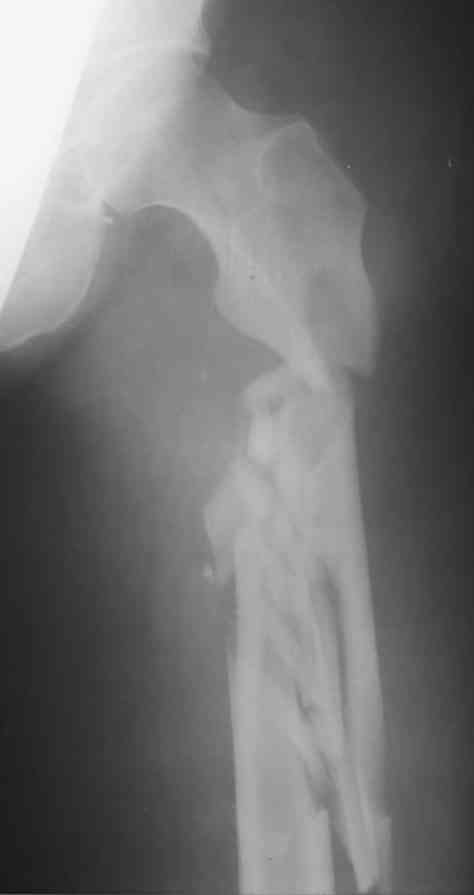

Перелом бедра

Не знаю что делать? Помогите, у кого есть какие мысли по фиксации данного перелома.